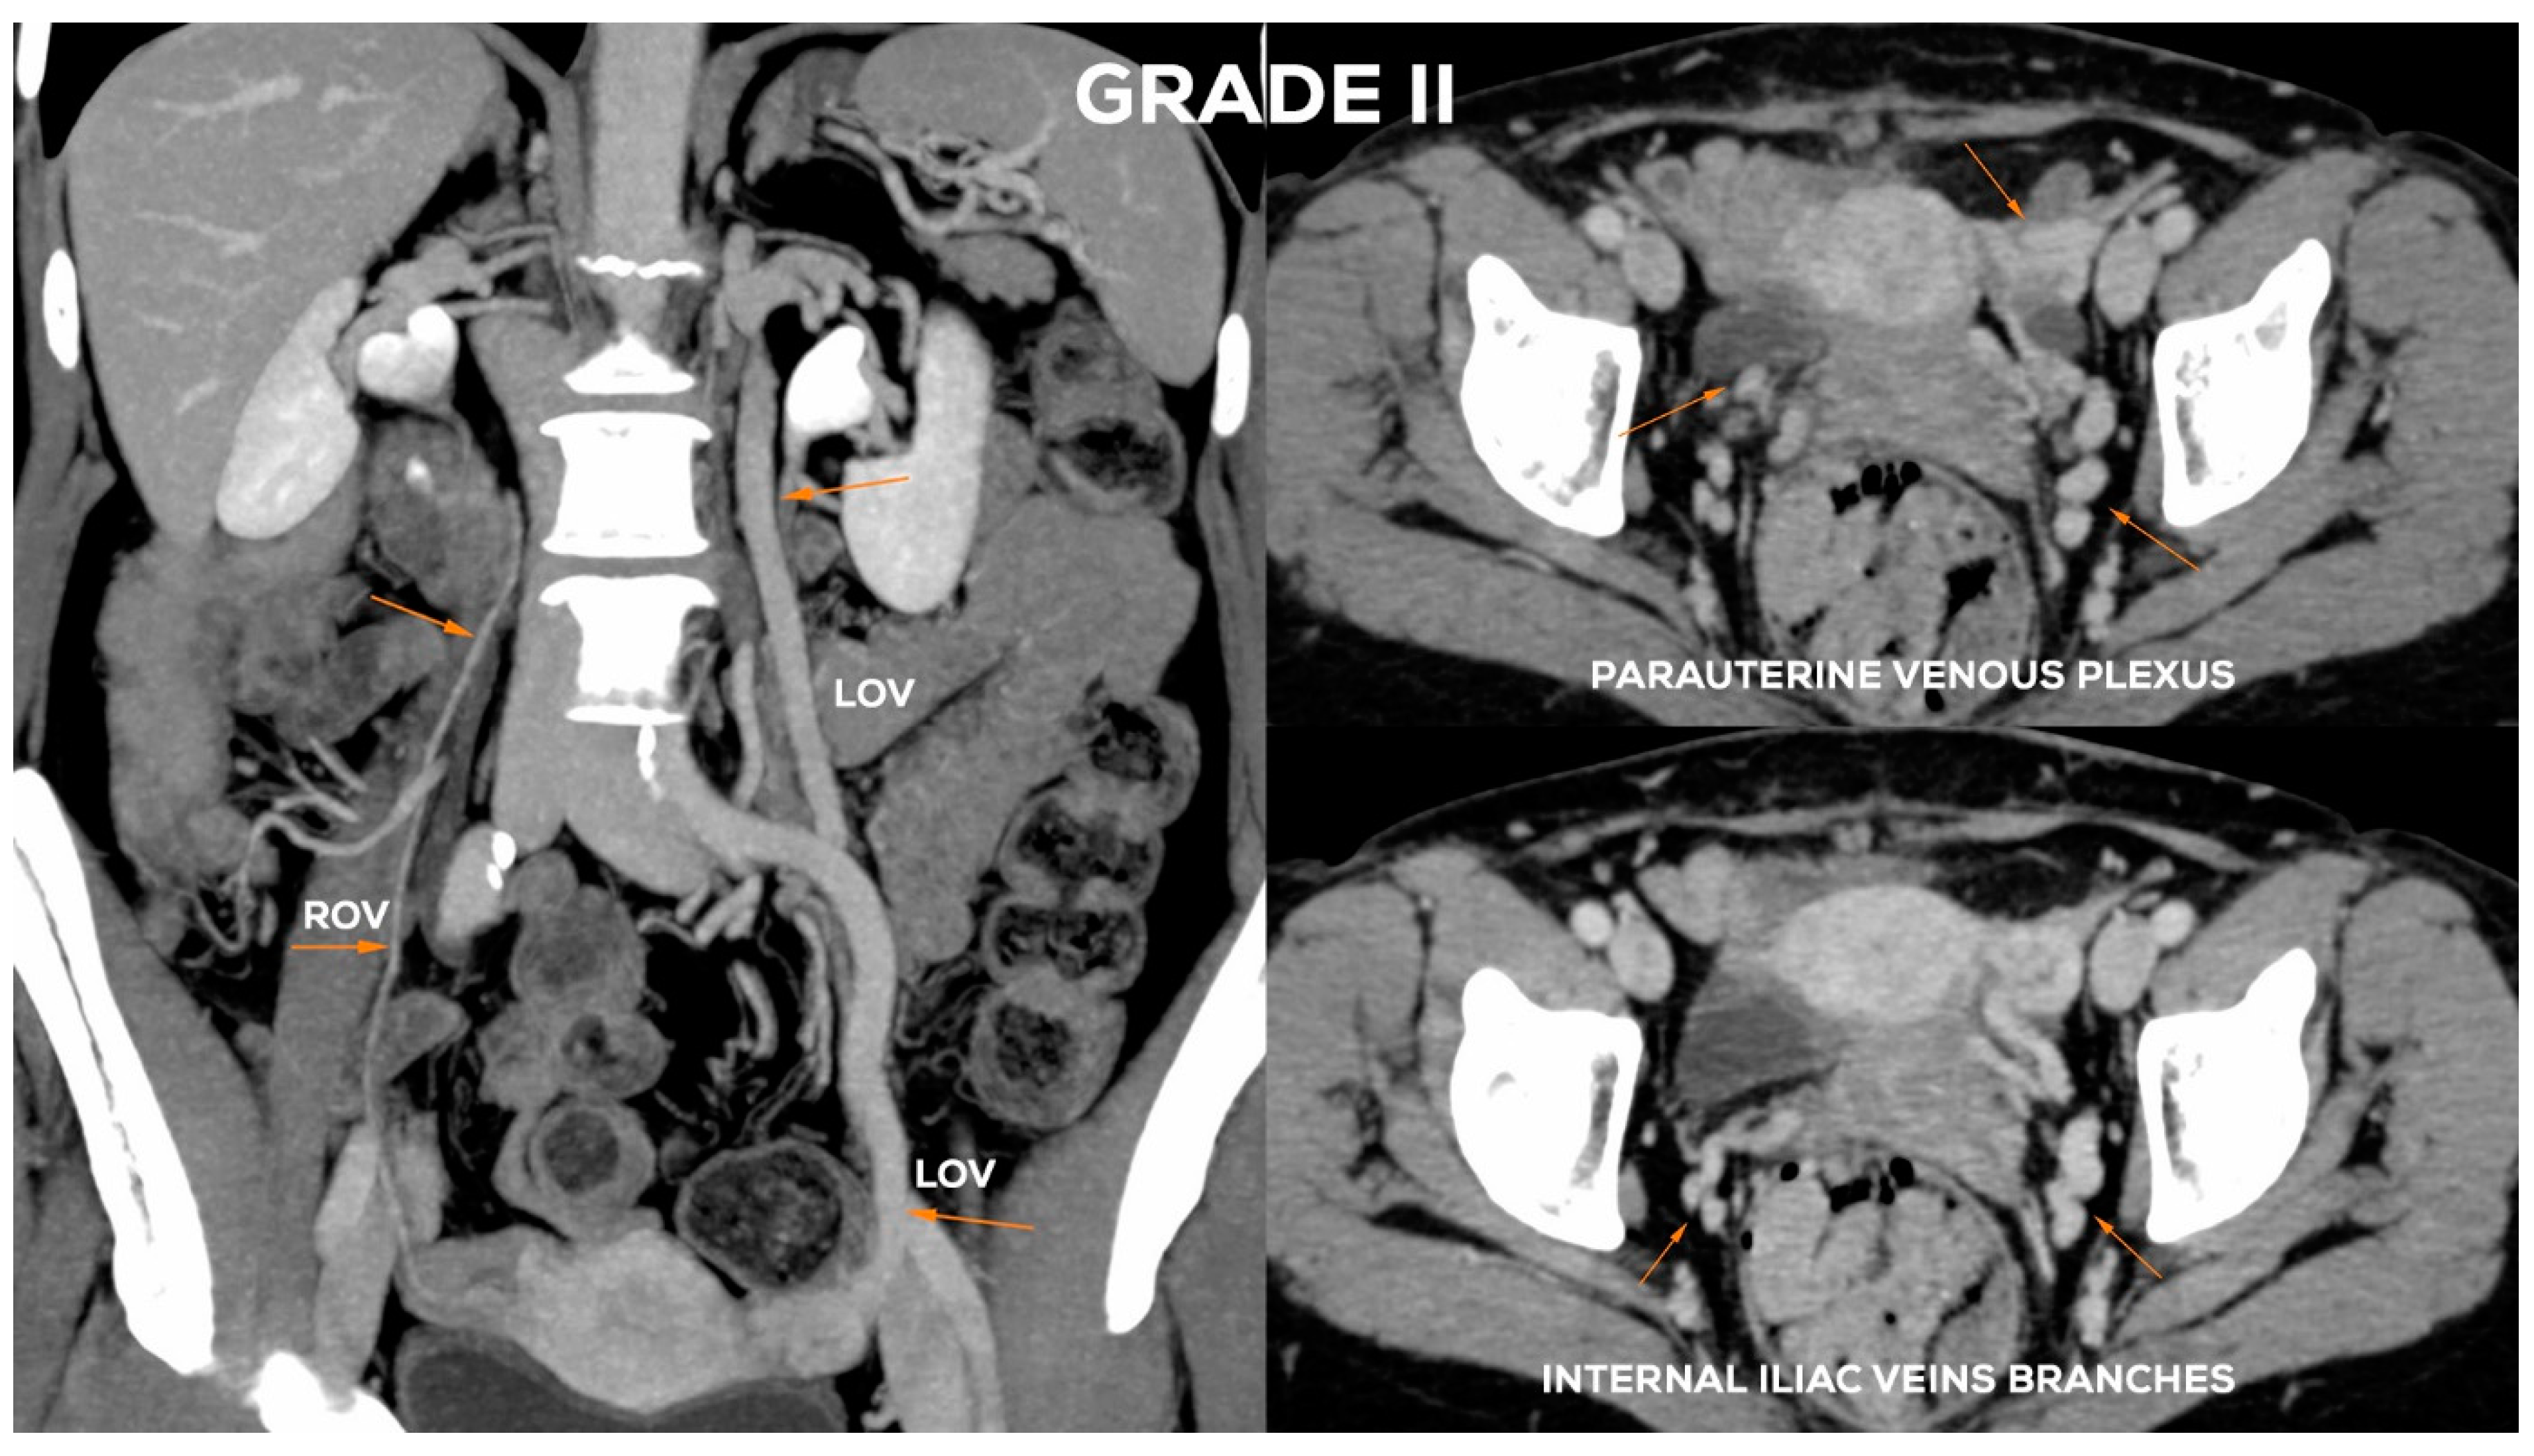

Figure 11.

Schematic illustration of ovarian veins insufficiency: Grade II (GII) and Grade II/III (GII/III).

4.2.4. Grade II/III (GII/III)

In the Grade II/III (Figure 11), the LOV trunk shows a clear insufficiency with dilatation up to 7.5–8 mm. Grade II/III distension of the left para-uterine venous plexuses is significant, usually up to 7 mm. The LIILV runoff is also dilated. Often the uterine vein or another branch of the LIILV (bLIILV) drainage becomes wider, even up to 6.5–7 mm. With GII/III insufficiency, there is a gradual volumetric overload of the right side with the distension of the lower ROV segment (ØROV up to 5.5–6 mm). The lower part of ROV when evaluated during the Valsalva maneuver or in a sitting position shows venous reflux. The middle and upper segment of the ROV is still efficient, although usually moderately widened. The venous plexuses of the right para-uterine region continue to distend (rPUV up to 6–6.5 mm). RIILV runoff (bRIILV up to 6 mm) is overloaded (Figure 13).

Figure 13.

Typical findings in patient with Grade II/III ovarian veins insufficiency seen on CTV images in coronal and axial planes.